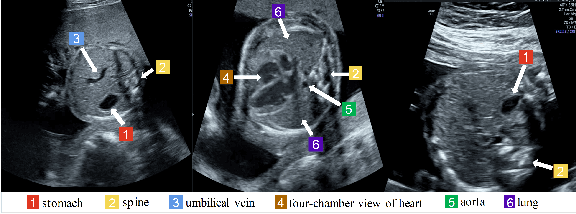

Abstract:Standard plane recognition plays an important role in prenatal ultrasound (US) screening. Automatically recognizing the standard plane along with the corresponding anatomical structures in US image can not only facilitate US image interpretation but also improve diagnostic efficiency. In this study, we build a novel multi-label learning (MLL) scheme to identify multiple standard planes and corresponding anatomical structures of fetus simultaneously. Our contribution is three-fold. First, we represent the class correlation by word embeddings to capture the fine-grained semantic and latent statistical concurrency. Second, we equip the MLL with a graph convolutional network to explore the inner and outer relationship among categories. Third, we propose a novel cluster relabel-based contrastive learning algorithm to encourage the divergence among ambiguous classes. Extensive validation was performed on our large in-house dataset. Our approach reports the highest accuracy as 90.25% for standard planes labeling, 85.59% for planes and structures labeling and mAP as 94.63%. The proposed MLL scheme provides a novel perspective for standard plane recognition and can be easily extended to other medical image classification tasks.